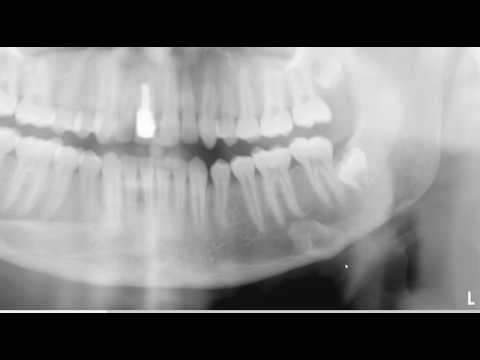

Anatomical Landmarks Found in a Panoramic Radiograph